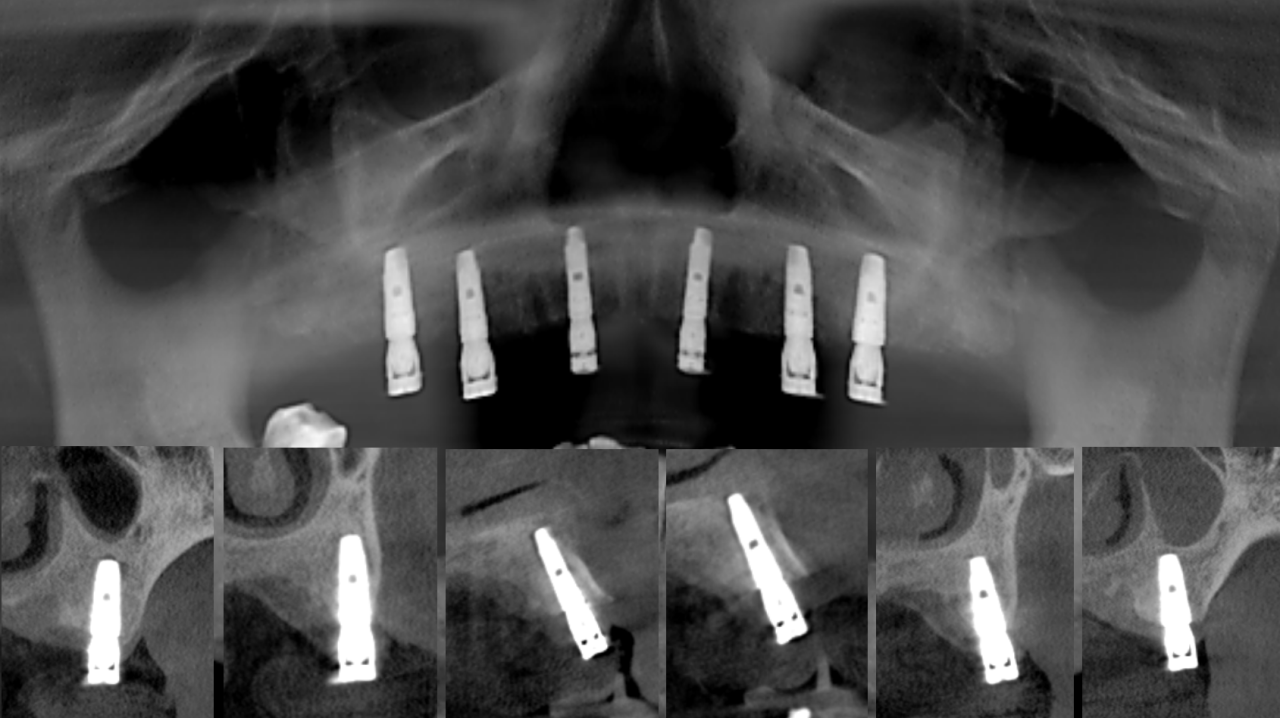

X线检查:上颌余留牙牙槽骨吸收至根尖1/3,预留骨量尚可,骨密度II-III类。

CT检查:后牙余留骨量高度10-12mm,前牙骨高度12-14mm,宽度均大于6mm。

方案设计:

导板制作完成:

导板引导下种植手术:

上颌植入6颗中科安齿种植体